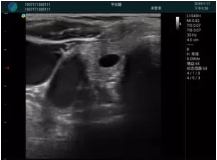

清晰顯示孕囊,通過(guò)軟件包計算孕齡7w+6d

M20實(shí)時(shí)引導,術(shù)中清晰顯示孕囊被破壞和抽吸針的過(guò)程,清晰顯示吸引針

抽吸結束后縱切子宮,孕囊已被完全抽吸,未見(jiàn)明顯殘留

橫切子宮,發(fā)現右側宮腔靠近宮角處有少許脫模樣殘留

M20引導下,抽吸針找到右側宮角處再次清掃

二次抽吸后再次進(jìn)行超聲檢查,宮腔未見(jiàn)殘留,宮腔線(xiàn)清晰顯示